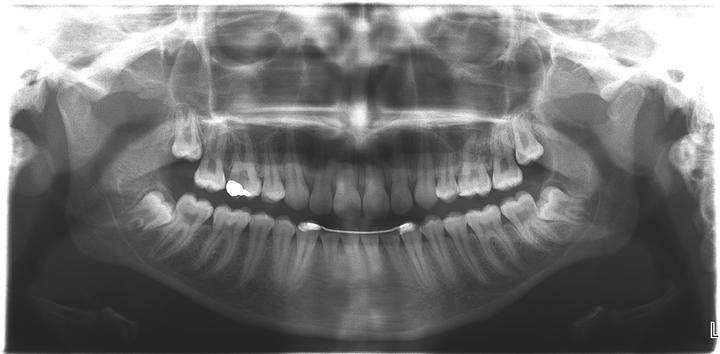

L’extraction des dents de sagesse consiste à enlever les troisièmes molaires du haut et/ou du bas. Chez l’enfant ou l’adolescent, ces dents n’ont pas terminé leur développement et sont appelés germes (l’intervention est appelée « germectomie »).

Ces dents doivent être extraites parce qu’elles sont en mauvaise position et sont à l’origine de douleurs et d’inflammation ou parce qu’elles risquent de perturber le bon alignement des dents chez l’enfant ou l’adolescent (l’indication est souvent portée par l’orthodontiste) .